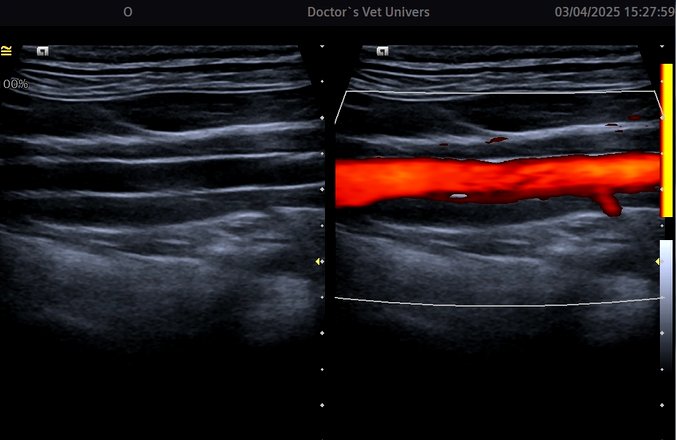

Angioplastia şi Stentarea în Boala Ocluzivă Ateromatoasă a Aortei Infrarenale (patologie extrem de rar întâlnită) la un câine de 16 ani realizată cu succes în premieră în România (şi rar efectuată la nivel internaţional) de către echipa AvantGarde CardioTeam în cadrul Laboratorului de Radiologie Intervenţională Veterinară “Doctor’s Vet Univers” Bucureşti, România.

Angioplasty and Stenting in Atheromatous Occlusive Disease of the Infrarenal Aorta (extremly rare diagnosed pathology) in a 16 years old dog successfully performed for the first time in Romania (and rarely effectuated internationally) by the AvantGarde CardioTeam in the Veterinry Interventional Radiology Laboratory “Doctor’s Vet Univers” Bucharest, Romania.